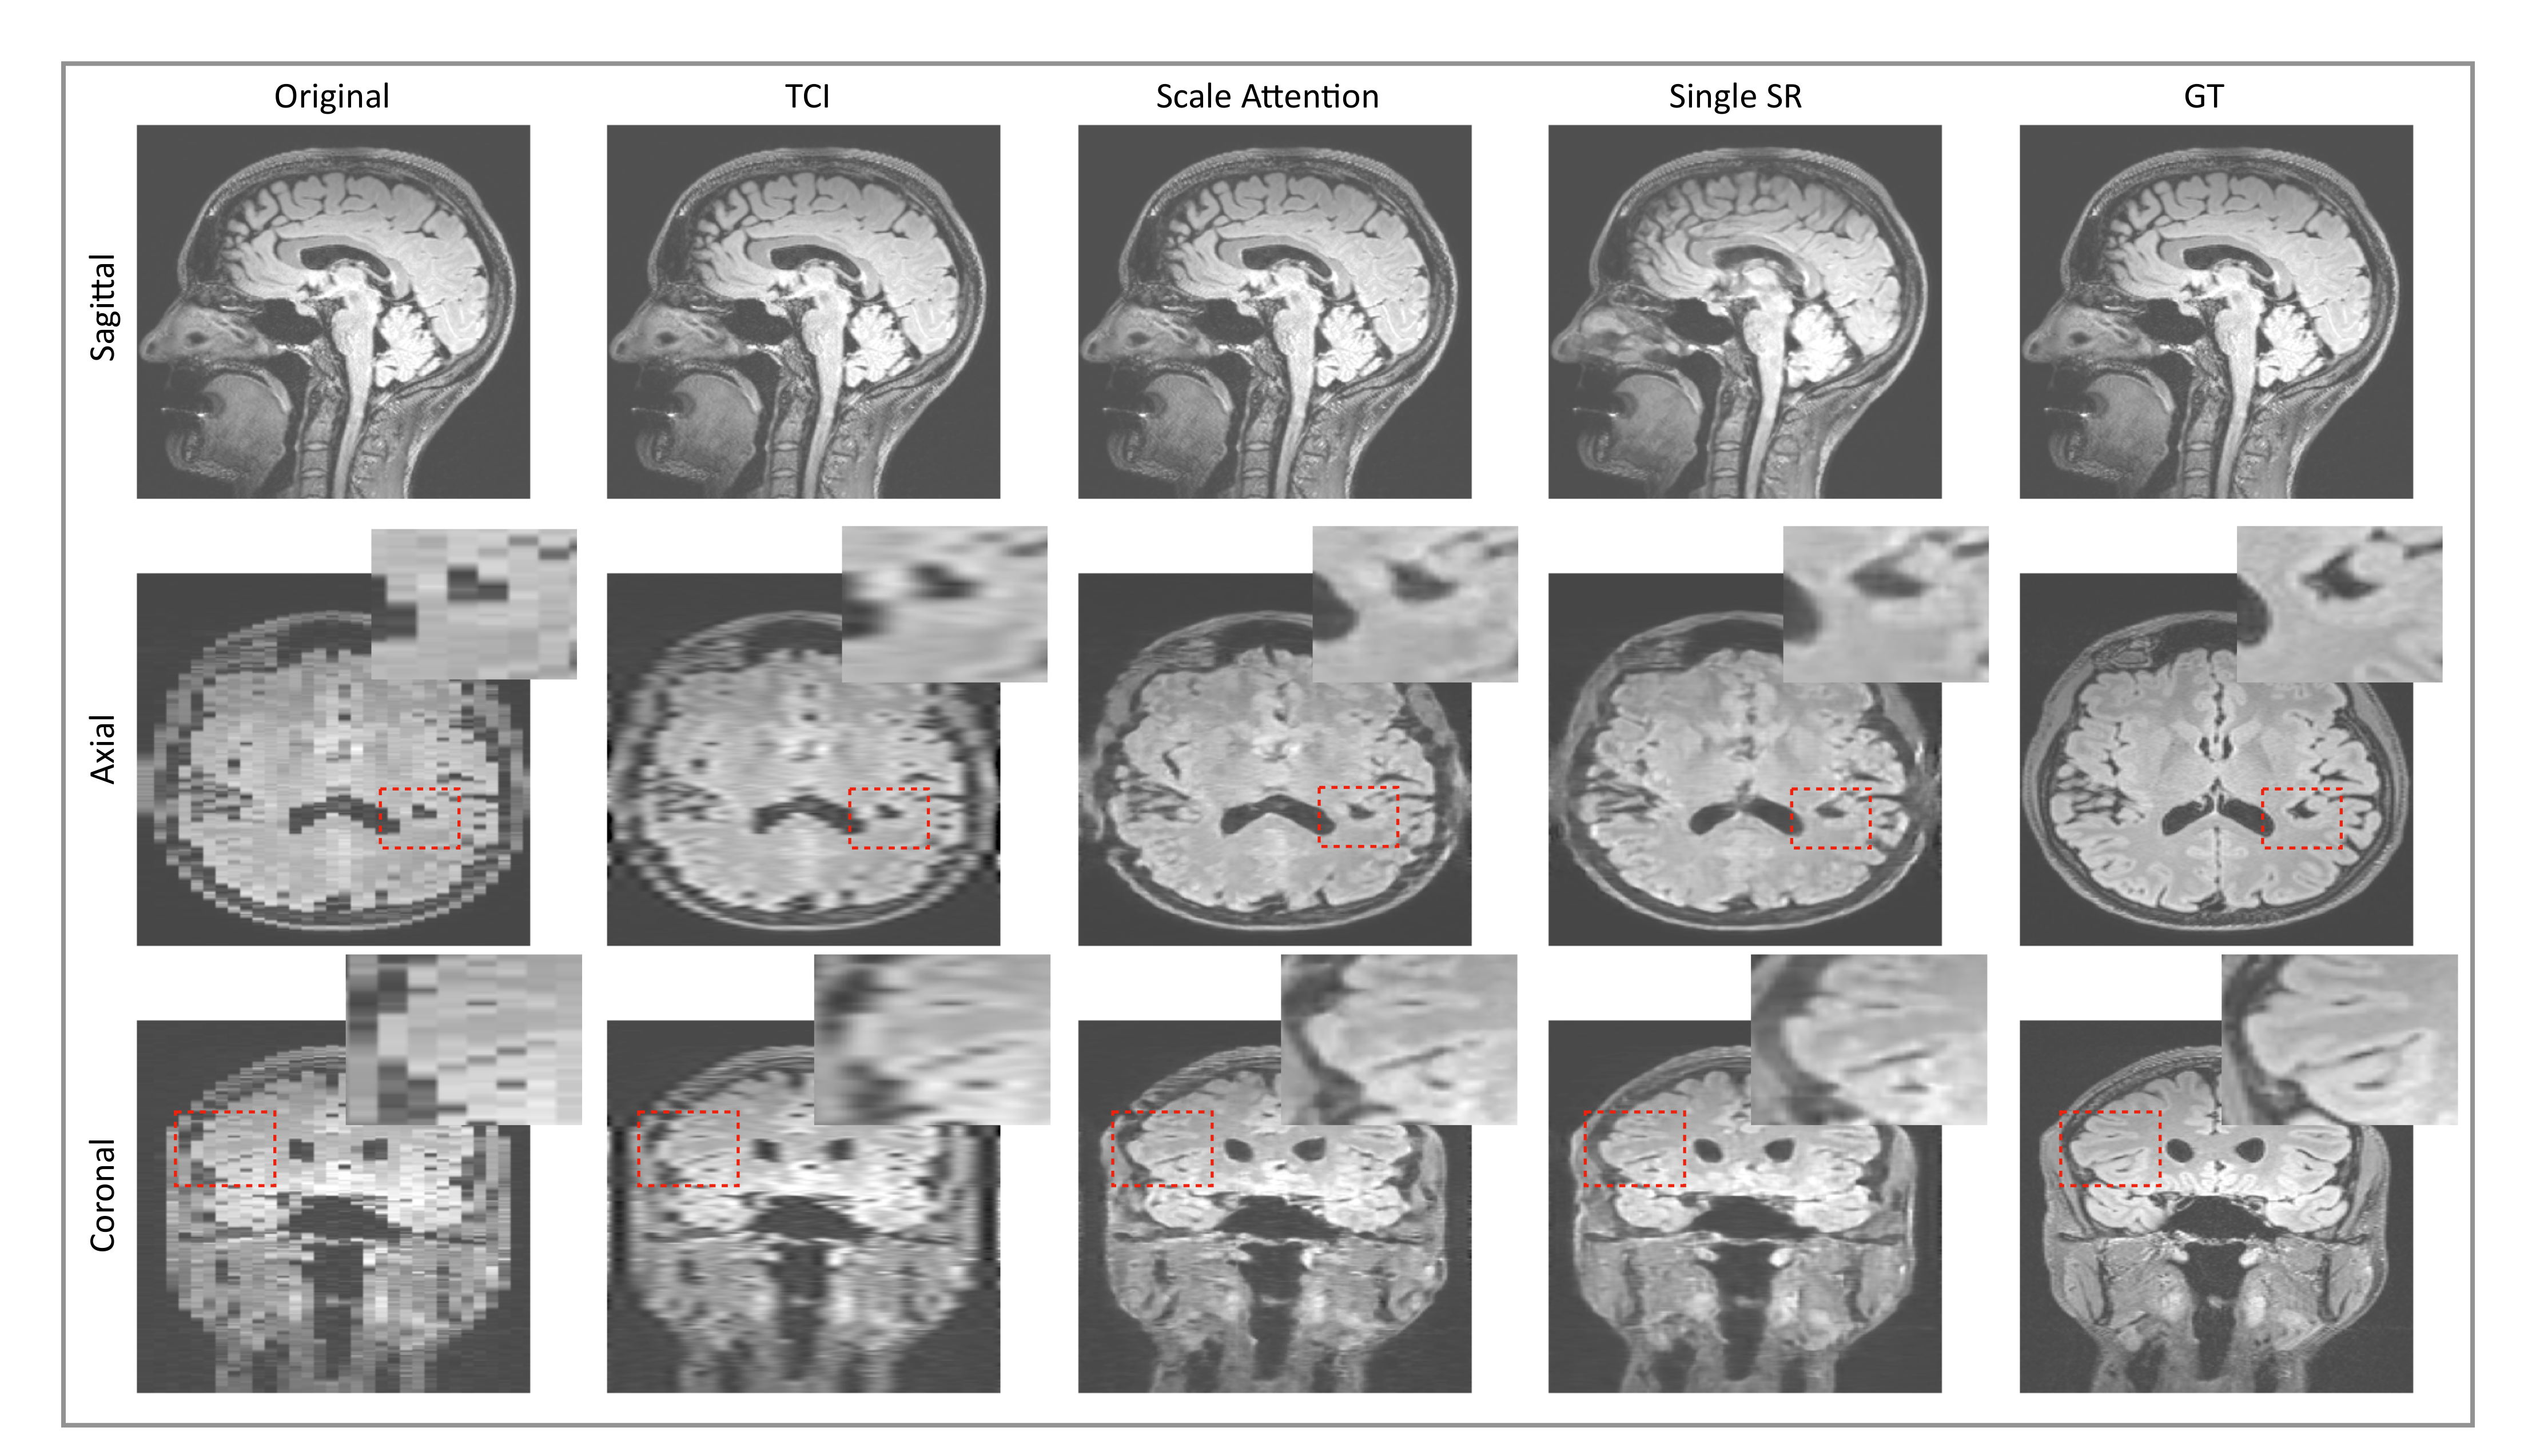

As discussed in Section 2, pixel-wise loss usually achieves a relatively high metric score but fails in resolving the textures, edges, and high-frequency details, resulting in blurring of the images that are produced. The scheme that we propose generalizes the application of perceptual loss previously defined on 2D pre-trained VGG to study single-image SR onto 3D medical images. Through this simple but effective idea of importing all the projected slices along the three principal directions into the pre-trained VGG, we observed that the 3D MRI volume can be perceptually resolved (see the ablation study Figure 8). SOUP-GAN was compared to another MRI SR approach called “DeepResolve”, both of which focus on thick-slice to thin-slice reconstruction. The two test datasets included in Figure 8 are the T1-weighted brain MRI (reformatted coronal images in the first row, and reformatted sagittal images in the second), and knee MRI in the third row. The images appear better compared to the original thick slices, the cubic-spline interpolated images, and the MSE results. They are further improved by 3D perceptual loss with GAN, achieving the highest perceptual quality. Besides the three principal directions (e.g., axial, sagittal, and coronal), we noted that oblique planes are also able to be resolved through multi-planar reconstruction with our 3D perceptual-loss strategy (unpublished data). We used a ’vanilla’ GAN instead of more advanced GANs, e.g., Wasserstein [45] or Relativistic GAN [46], since the vanilla GAN performs well for our training.

Figure 8.

Ablation study: Test examples on brain and knee MRI showing perpendicular reconstructions from original thick slices, using TCI, MSE, and GAN using 3D perceptual loss (SOUP). We note that [32] proposed a single-scale residual-based 3D convolutional neural network with MSE, similar to the third column here. Our SOUP approach better resolves the perceptual details and is more generally applicable to various sampling factors and different imaging modalities. TCI: tricubic interpolation.